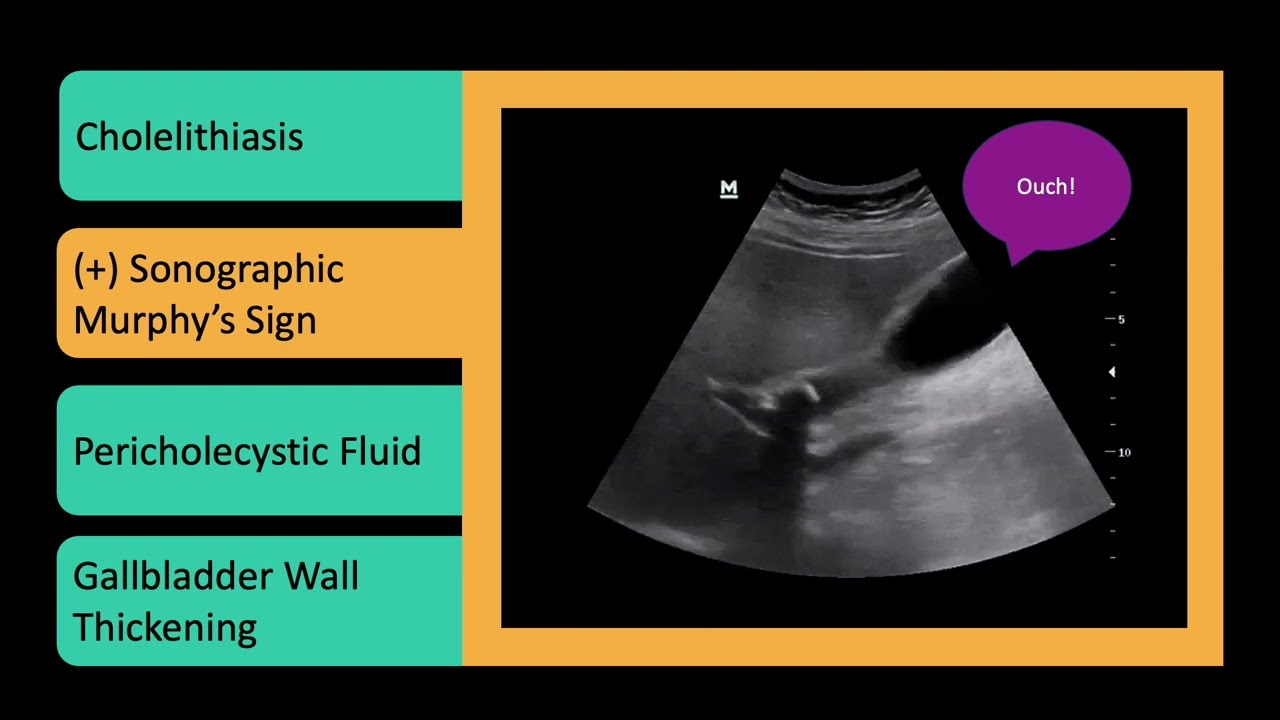

Right upper quadrant pain? POCUS to the rescue. In this detailed lesson, you’ll learn how to assess the gallbladder and biliary system using point-of-care ultrasound—an essential skill for evaluating abdominal pain quickly and accurately.

🔥 Recognize signs of acute cholecystitis (wall thickening, pericholecystic fluid, sonographic Murphy’s sign)

Keywords: Gallbladder Ultrasound, Biliary POCUS, Gallstones, Cholecystitis, Sonographic Murphy Sign, Common Bile Duct Dilation, RUQ Pain, Family Medicine Ultrasound, Abdominal POCUS